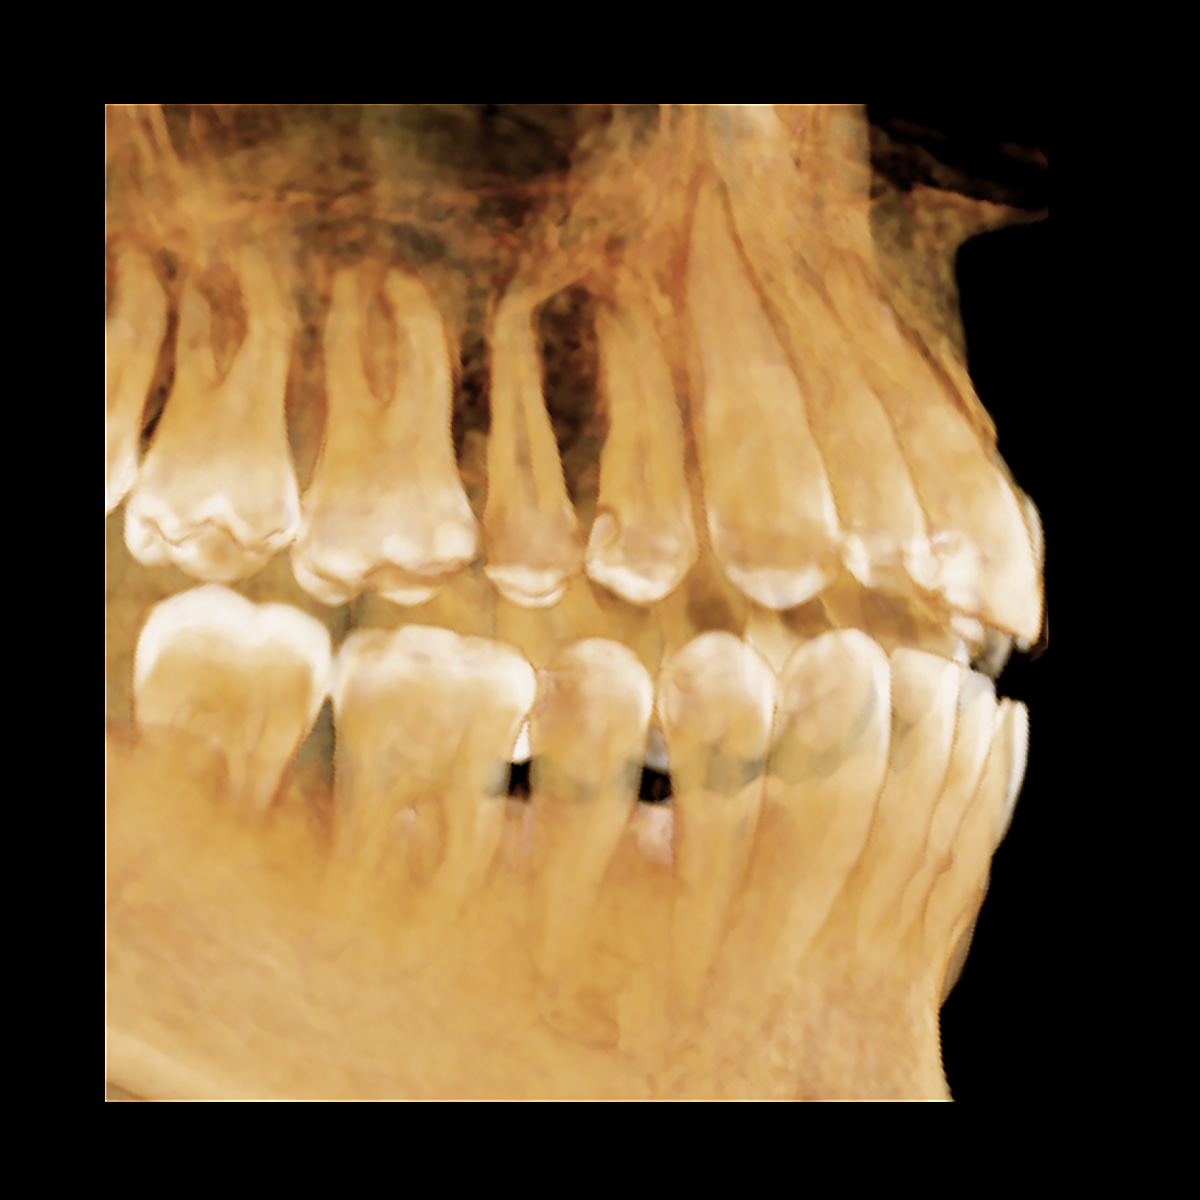

U Dental Scan centru pružamo CBCT FOKUS snimak vilice – preciznu 3D dijagnostiku manje regije vilica uz minimalnu dozu zračenja. Idealno rešenje za situacije kada je potrebno fokusirano snimanje jednog segmenta bez izlaganja celih vilica sa ramusom i sinusima.

Precizni snimak 8×8 cm određene strane gornje i donje vilice koji obuhvata sve zube gornje i donje vilice u zoni snimanja. Centralna zona od 5 do 5 obe vilice, Leva zona od 4 do umnjaka obe vilice – levo, Desna zona od 4 do umnjaka obe vilice – desno.

- Manje polje snimanja (FOV) – precizna dijagnostika fokusirana na regiju od interesa

- Visoka rezolucija – kristalno jasan prikaz struktura